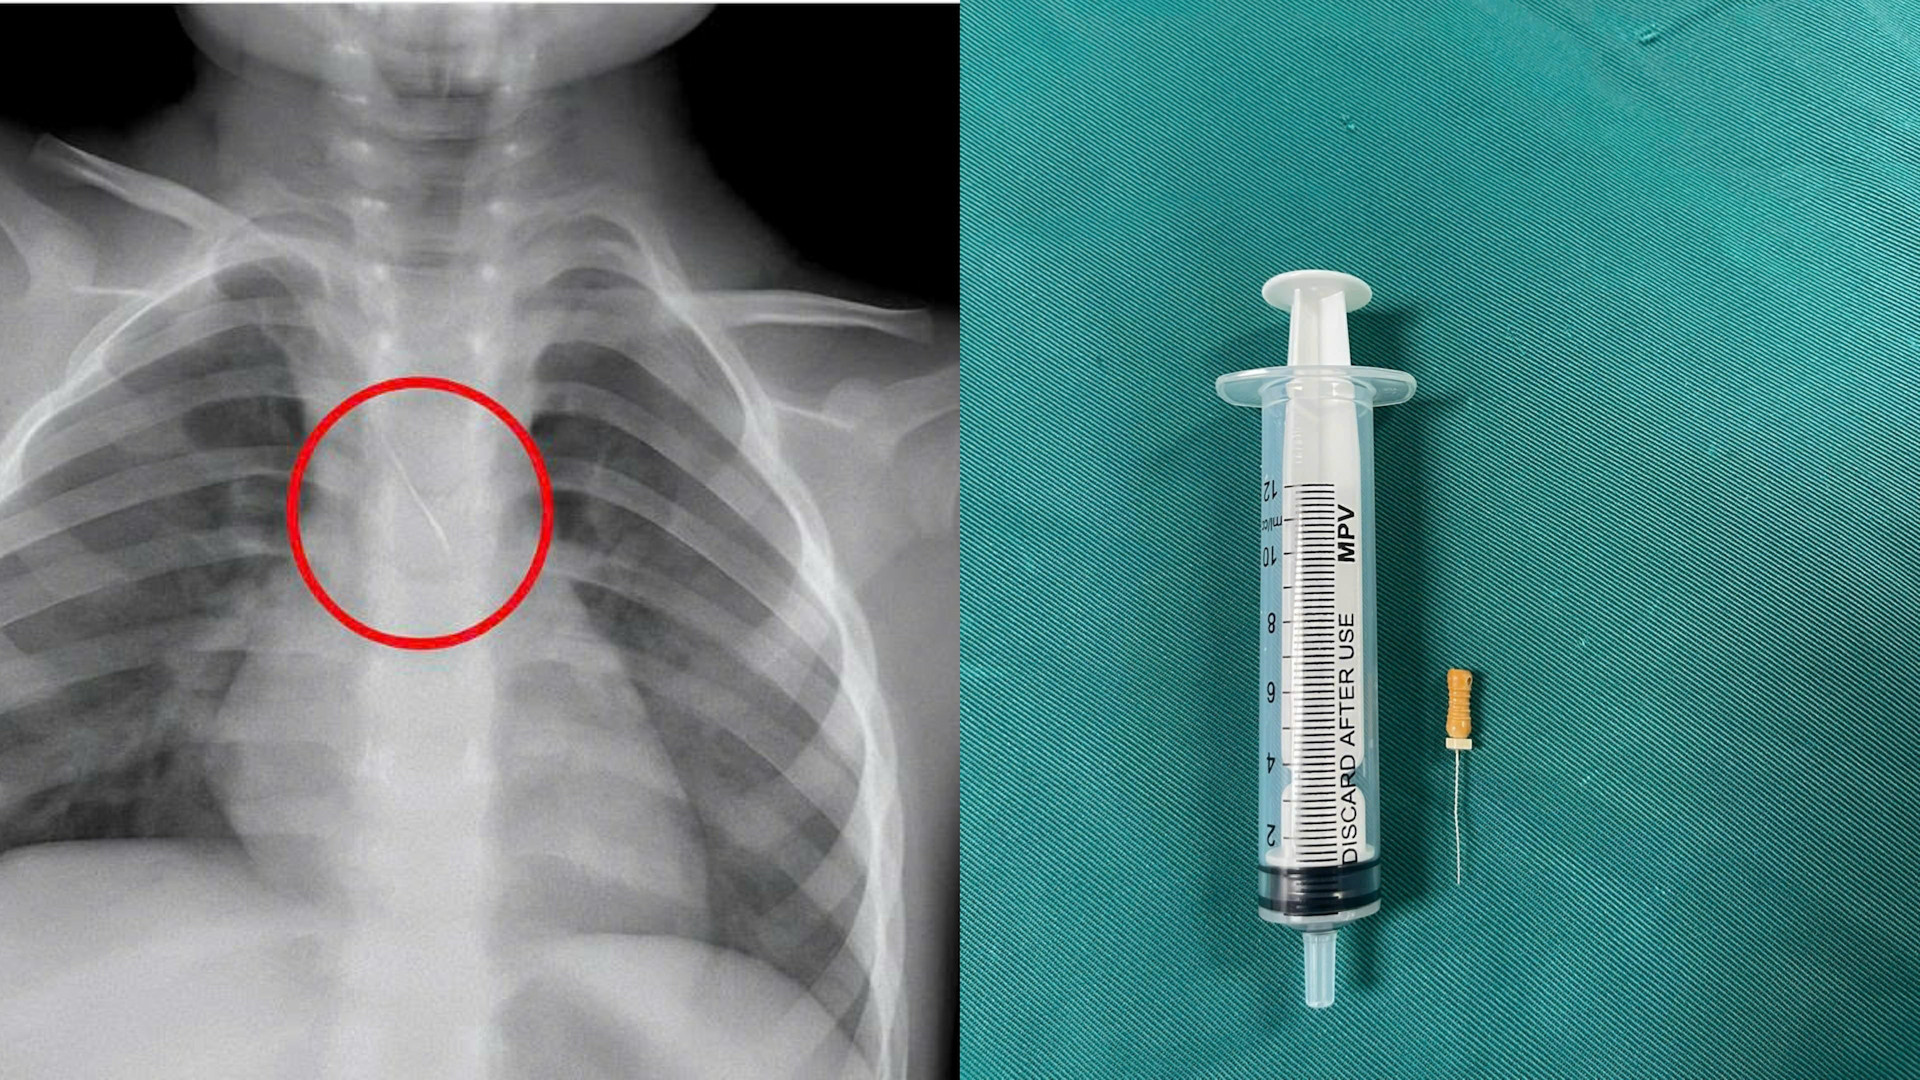

Trước đó, bệnh nhi N.Q.T.Đ. (3 tuổi, trú tại xã Cửa Việt) nhập viện trong tình trạng ho nhiều, ho sặc. Kết quả chẩn đoán hình ảnh cho thấy, bệnh nhi bị sặc kim chọc tủy vào đường thở.

Dị vật này dài khoảng 22mm, nằm ở góc carina (nơi vùng chia đôi khí quản), một đầu nhọn cắm vào 1/3 dưới khí quản, một đầu tròn nằm trong phế quản gốc trái.